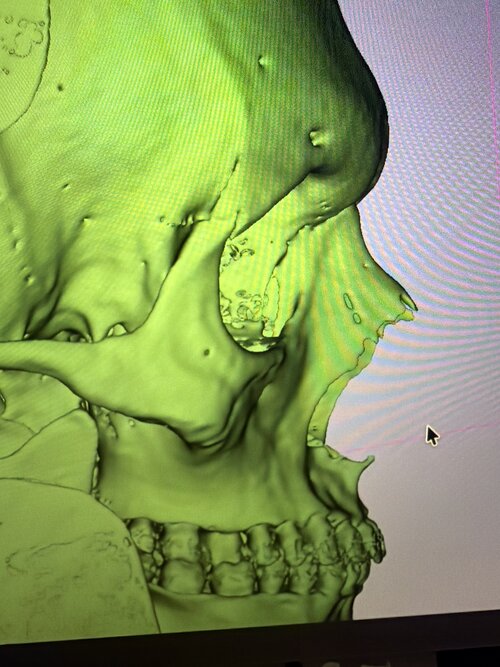

I know I need chin, flared gonian etc. but what else? Specifically I'm worried about my under eye hollows and lack of midface support, is it a soft tissue issue for me or lack of bone? What is the best solution to fix it? Fat grafts? Implants? Some crazy skull splitting procedure?

I have pretty thick skin and what looks like dog shit tier fat distribution, so maybe it's just fat + thick heavy skin sagging into nasolabial folds? Even if that's the case idk what I need. Fat grafts?

Every AI I have asked said I have neutral orbital vector not negative, good maxilla projection xygo projection etc but I feel like it's gaslighting me tbh

I have pretty thick skin and what looks like dog shit tier fat distribution, so maybe it's just fat + thick heavy skin sagging into nasolabial folds? Even if that's the case idk what I need. Fat grafts?

Every AI I have asked said I have neutral orbital vector not negative, good maxilla projection xygo projection etc but I feel like it's gaslighting me tbh